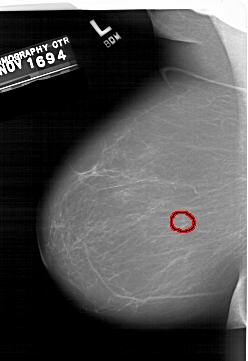

A_1406_1.RIGHT_CC

RIGHT_CC LINES 6871 PIXELS_PER_LINE 4051 BITS_PER_PIXEL 12 RESOLUTION 43.5 NON_OVERLAY

FILE: A_1406_1.LEFT_MLO.OVERLAY

TOTAL_ABNORMALITIES 1

ABNORMALITY 1

LESION_TYPE CALCIFICATION TYPE PUNCTATE DISTRIBUTION CLUSTERED

ASSESSMENT 4

SUBTLETY 4

PATHOLOGY BENIGN

TOTAL_OUTLINES 1